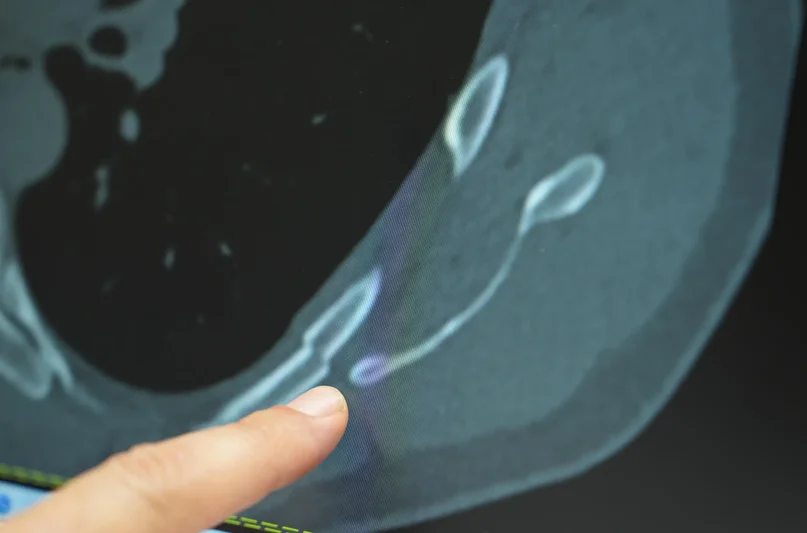

Ani başlayan ve geçmeyen göğüs ağrısı genç yaşlarda da ciddi kemik problemlerine işaret edebilir. Medipol Sağlık Grubu’ndan Göğüs Cerrahisi Uzmanı Prof. Dr. Güven Sadi Sunam, genç hastalarda öksürüğe bağlı kaburga kırıklarının görülme sıklığının arttığını ve bu durumun altta yatan önemli nedenleri olabileceğini belirtti.

Göğüs ağrısı deyince akla yaşlılar gelir ama son dönemde gençlerde de öksürük sonrası kaburga kırıkları artış gösteriyor. Medipol Bahçelievler Hastanesi’nden Göğüs Cerrahisi Uzmanı Prof. Dr. Güven Sadi Sunam, genç yaşta görülen kaburga kırıklarının ardındaki gizli tehlikeleri ve korunma yollarını paylaştı.